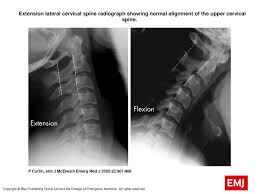

This procedure may be used to diagnose back or neck pain, fractures or broken bones, arthritis, degeneration of the disks, tumors, or other problems. Enter search terms and tap the search button. They show pictures of your internal tissues, bones, and organs. Please understand that our phone lines must be clear for urg. Here's what to expect with this painless procedure and why your dentist may recommend it.

This procedure may be used to diagnose back or neck pain, fractures or broken bones, arthritis, degeneration of the disks, tumors, or other problems. It's commonly done after someone has been in an automobile or other accident. They show pictures of your internal tissues, bones, and organs. Here's what to expect with this painless procedure and why your dentist may recommend it. Please understand that our phone lines must be clear for urg. Enter search terms and tap the search button.